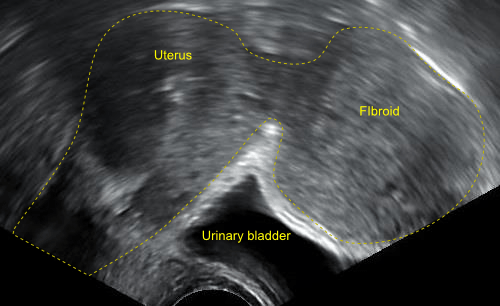

महिलाओं के यूटेरस में होने वाले असमान्य विकास को हम फाइब्रॉइड्स या रसौली कहते हैं। इस असमान्य विकास की वजह से यूटेराइन कैंसर होने का खतरा नहीं होता लेकिन कुछ मामलों में ये ट्यूमर का रूप ले सकते हैं, जिसकी वजह से पीरियड्स के समय बहुत दर्द रहेगा और सामान्य से ब्लीडिंग हो सकती है।

फाइब्रॉइड्स गर्भाशय में किस स्थान पर है इसके अनुसार फाइब्रॉइड्स को पांच भागों में बांटा गया है।

ये फाइब्रॉइड्स गर्भाशय के बाहर पाई जाने वाली दीवार पर पाई जाती है। यह आंत, रीढ़ की हड्डी और ब्लैडर पर दबाव डालता है। इसके कारण पेल्विस में तेज दर्द होता है।